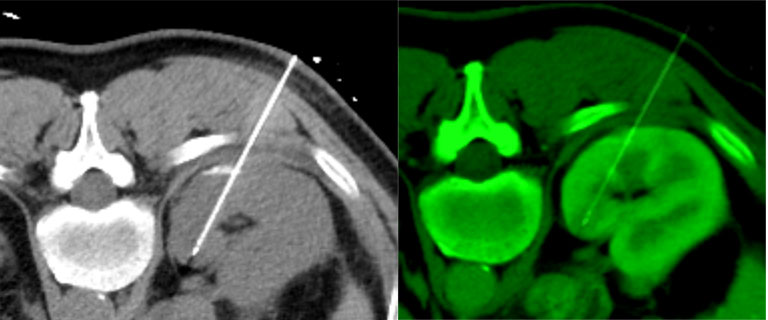

IGTFusion used to guide and confirm accurate needle placement in 3 renal lesions that were not visible on CT during the procedure.

- Registered a supine pre-procedural image to a prone procedural image

- Saved procedure time by eliminating the need to constantly refer back to the pre-procedural image

- Reduced the clinician tedium of estimating the accuracy of needle placement